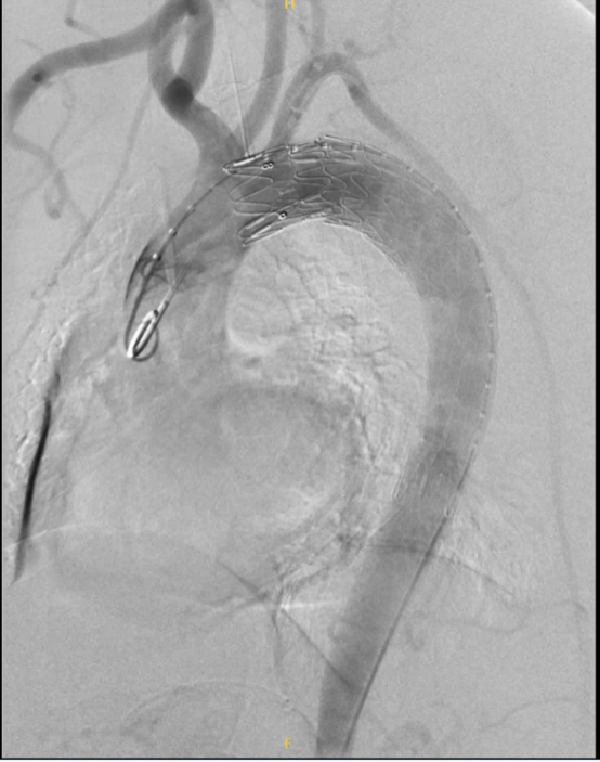

通过下面4个具体病例进一步说明TEVAR在治疗复杂型B型主动脉夹层中的治疗原则、注意事项及应用。

★病例4

急性复杂性AD

早期干预的重要性:急性复杂型TBAD的高风险性和对患者生命的重大威胁,需要早期临床干预,TEVAR是首选治疗方法。

TEVAR的多方面作用:不仅能够封堵原发破口,还能扩大真腔供血,从而降低死亡率和并发症发生率。